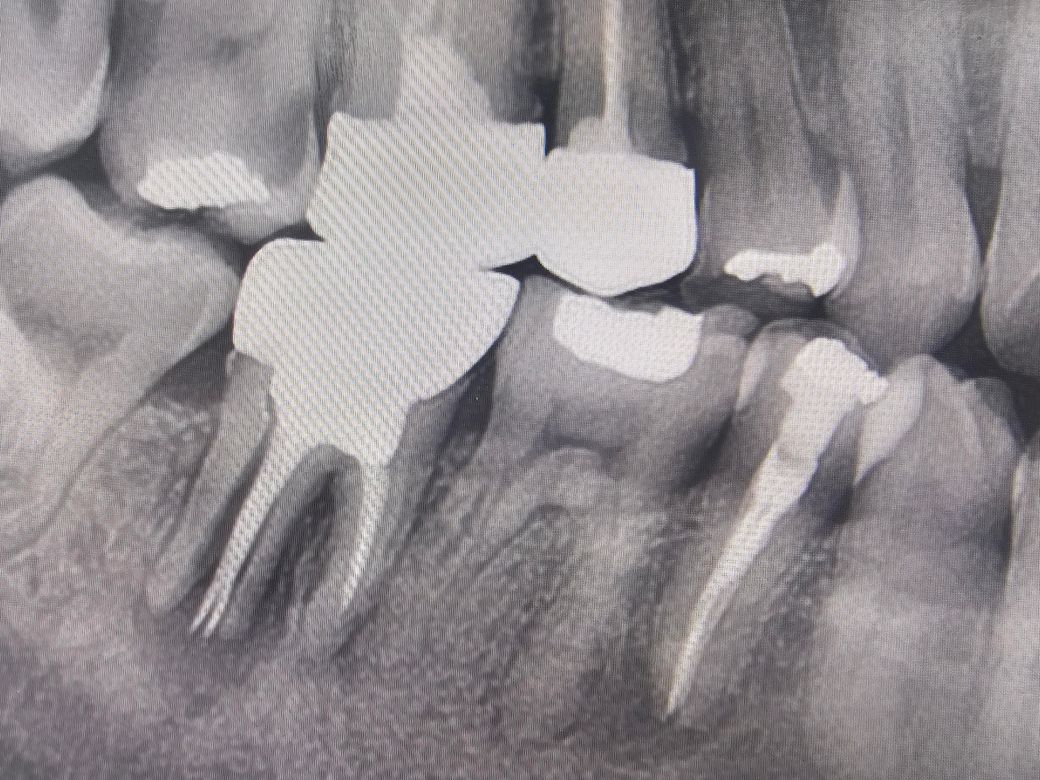

이 치아 꼭 임플란트 해야 하는건가요??

오른쪽 어금니인데 치아 뿌리가 x-ray상 저렇게 나오는데치과에서는 임플란트 해야 한다고 하네요. 통증은 아예 없는데, 그냥 쓰면 안되고 꼭 임플란트 해야 하는건가요?

사진상에 보이는 치아는 치아가 수직으로 깨진거 같습니다 .발치를 하시고 나서 임플란트를 하시는게 좋을것같습니다.

사진으로는 치아의 뿌리가 부러진것으로 보입니다. 치아의 뿌리가 부러진 경우에는 치아를 발치 해야 합니다

발치한 후에는 해당부위에 보철수복을 위해서 임플란트를 하는것이 좋을수 있습니다.

생니 아니고 치아뿌리 주위에 염증이 많이 진행되어 있어 지금도 뼈가 녹아있는 상태입니다. 두면 점점 더 뼈가 녹아 없어지기 때문에 가능한 빨리 치아를 뽑아 주어야 합니다. 임플란트는 그 다음 문제입니다.

엑스레이상 치아뿌리 하방 잇몸뼈로 염증은 있는 상태입니다 그냥 둘 경우 잇몸뼈가 점차 녹을 수 있습니다 발치를 원치 않는다면 치근단절제술 등을 고려해볼 수 있습니다

사진 상에 보이는 치아는 수명이 다 한 것으로 보이며 임플란트 외에 다른 치료방법은 힘든 것 같습니다.